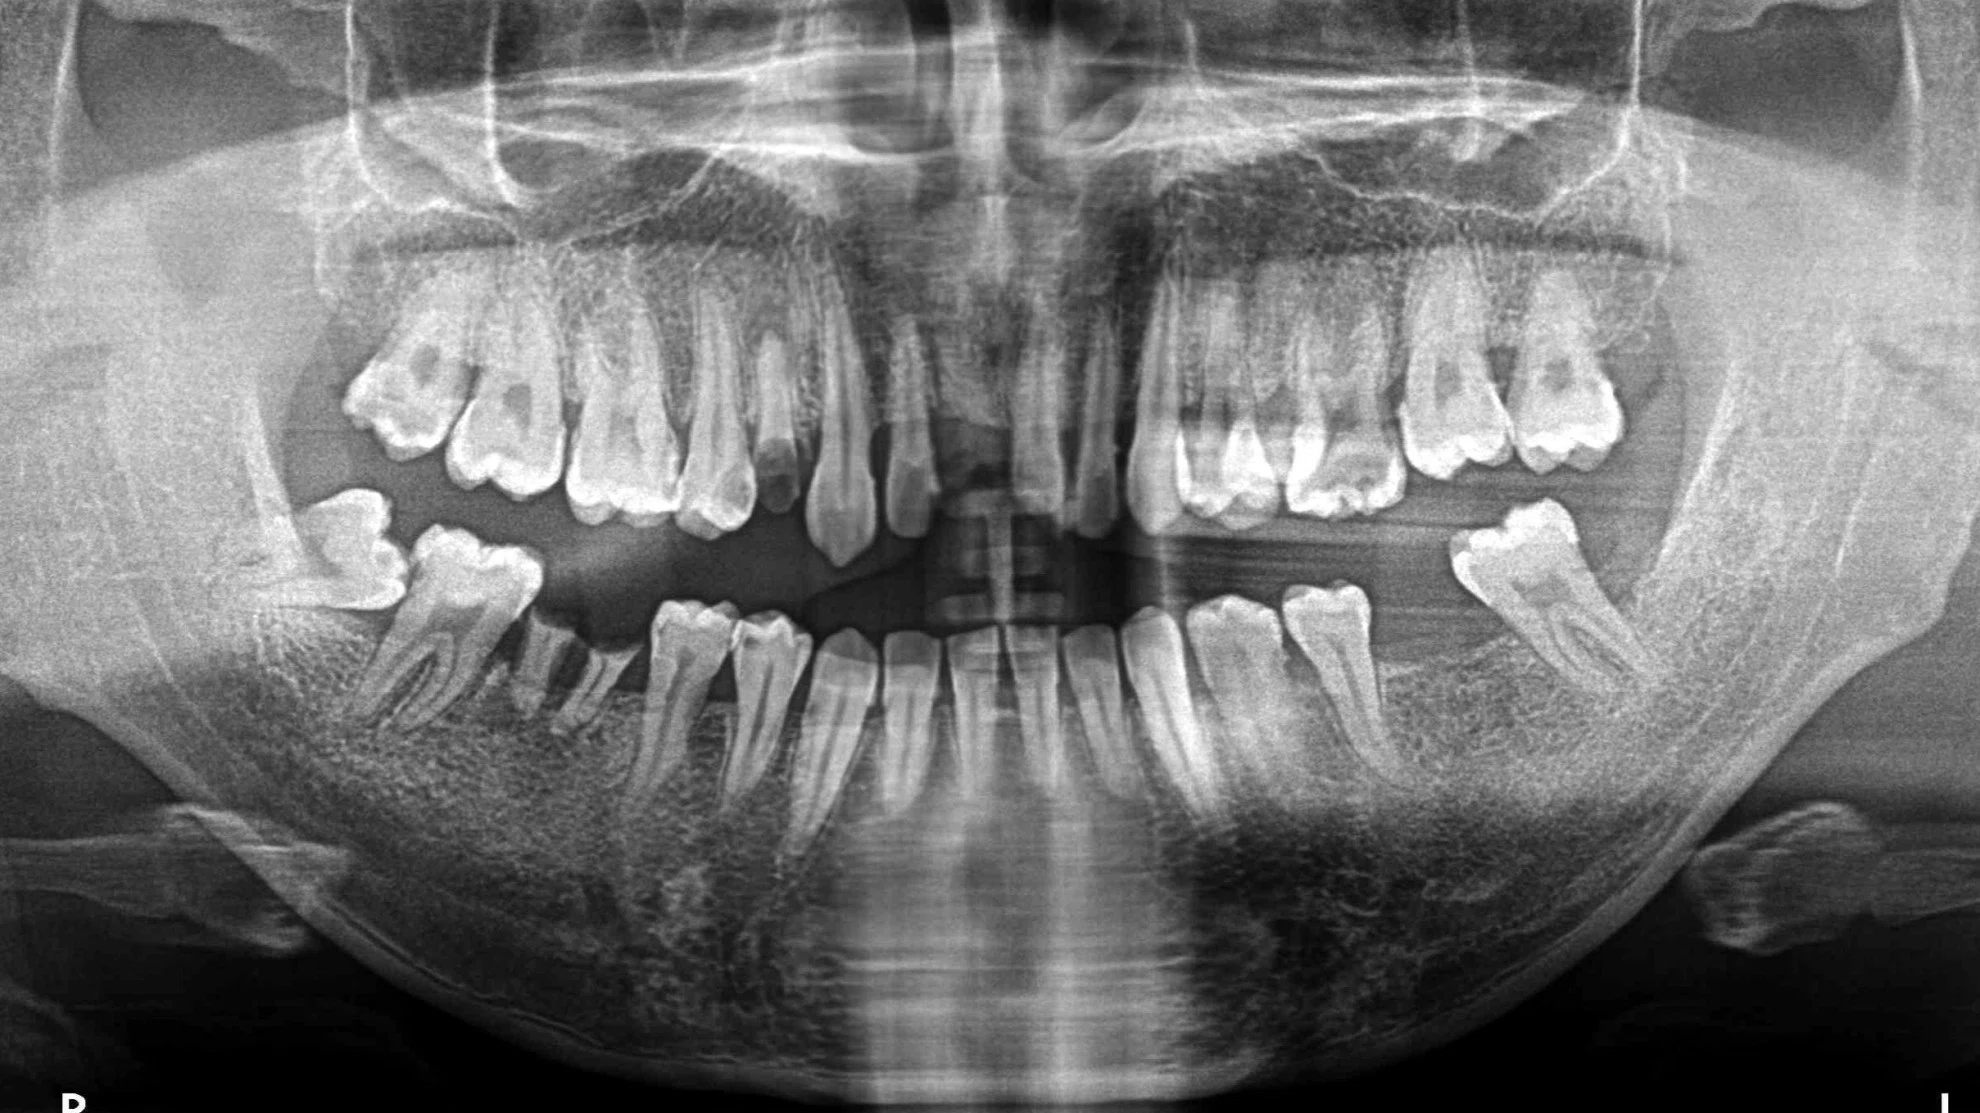

這位患者的治療挑戰涵蓋了缺牙、受損牙齒的修復,以及對最終美觀的極高要求。我們透過一系列數位化、微創化的治療流程,成功重建了患者的口腔健康與自信笑容。

| 後牙區 | 觀察到多處缺牙,可能伴隨齒槽骨條件的考量。 | 成功植入多顆人工牙根 (植牙),X光片顯示植體位置精準,骨整合情況良好,為恢復咀嚼功能奠定堅實基礎。 |

| 前牙區 | 可見多顆牙齒的齒質狀況與根尖健康需要處理。 | 根管治療成功完成,並搭配全瓷冠進行修復,重建了牙齒的形態與強度。 |